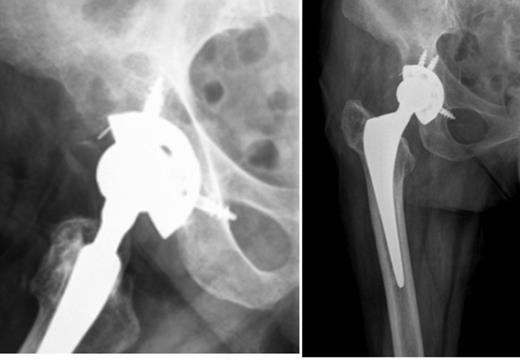

Given these findings, it was interpreted as aseptic loosening of the acetabular component and the patient was proposed for revision surgery. Two months later, when the patient was admitted for surgery, there was onset of right hip pain out of proportion associated with inability to walk, weight loss and respiratory symptoms. We asked for new pelvic and hip radiographs that showed an extensive osteolytic lesion with neoplastic appearance (Fig. 2).

Right hip radiographs (AP and lateral) at the admission, two months later, with an extensive osteolytic lesion in the right iliac wing